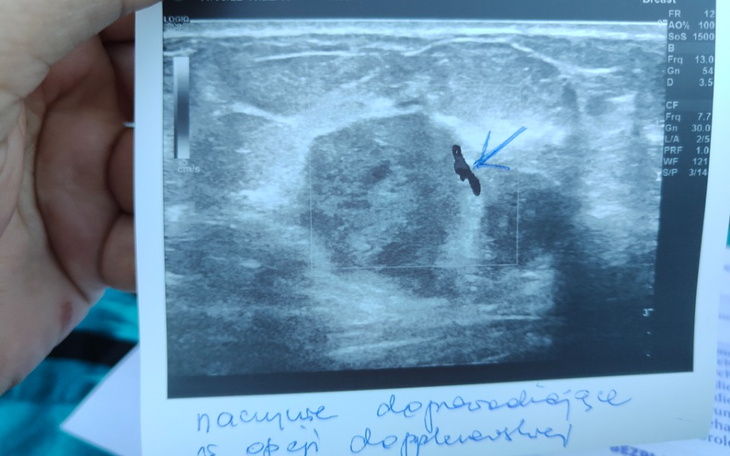

Dzień dobry. Mam na imię Małgosia. Mam 40 lat. W maju tego roku (2022) w badaniu USG piersi wykryto u mnie guza wielkości 13 mm x 14 mm.

Obecnie guz urósł do wielkości ponad 30 mm. Czeka mnie operacja i długi okres rekonwalescencji. Co wiąże się z pójściem na zwolnienie lekarskie, co obniży moja pensję (mam najniższą krajową) o 20%.